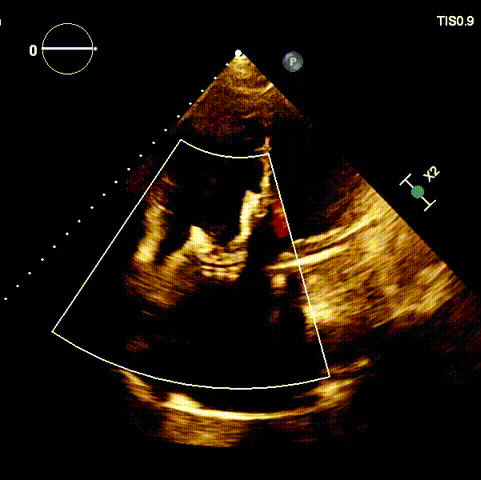

1.二尖瓣位機械瓣位置及功能未見異常;2.雙房及右室明顯擴大(左房收縮容積115ml,右房收縮容積370ml,右室中段左右徑65mm,右室FAC37%),下腔靜脈及冠狀靜脈竇擴張(下腔靜脈直徑44mm,冠狀靜脈竇直徑22mm);3.極重度三尖瓣反流(FTR 6+)。

術后超聲